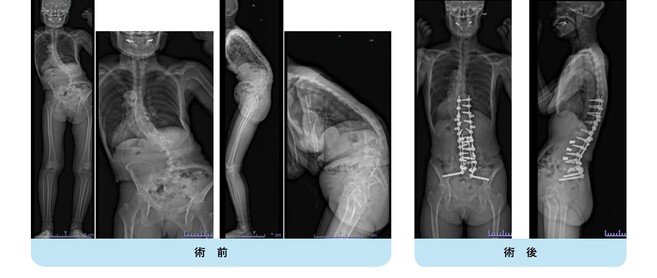

思春期特発性側弯症の全脊椎レントゲンで背骨が大きくSの字に曲がっています。最も曲がっている箇所は80°で、高度側弯に分類されます。後方からの脊柱側弯矯正術で真っ直ぐになっています。

また、側弯の患者さんは一般的にフラットバックと言って背骨の生理的後弯(背中の丸み)が失われています。この症例も胸椎後弯角は5°で典型的なフラットバックを呈しています(正常は20°~30°程度です)。この影響は頸椎の形態にも影響を及ぼし、この症例も頸椎が既に後弯(正常は前弯)しています。(黄色矢印)

ストレートネックという頸椎の前弯が消失して頸部の愁訴が出現する病態は広く知られていますが、更に変形が進行した頸椎と考えて下さい。

以前はこのフラットバック(生理的胸椎後弯の消失)を治すことは困難でしたが、当院では手術方法の様々な工夫により生理的胸椎後弯の復元を行っております。この症例は術後に胸椎後弯角が26°と改善しており、生理的な胸椎後弯が形成されています。さらに頸椎後弯にも良い影響を及ぼし、術後は頸椎前弯化が得られつつあるのが分かります。(黄色矢印)

他、側弯変形は必ず大なり小なりの回旋変形を伴います。脊柱の回旋変形は胸郭(肋骨)の回旋につながり、これにより側弯の患者さんは背中の片方が出っ張っています(多くは右)。リブハンプと言いますが、脊柱変形矯正によりこの回旋変形も改善します。この症例も術前に肋骨がかなり隆起していますが、術後にこの隆起がかなり減じているのが分かります。(赤色矢印)